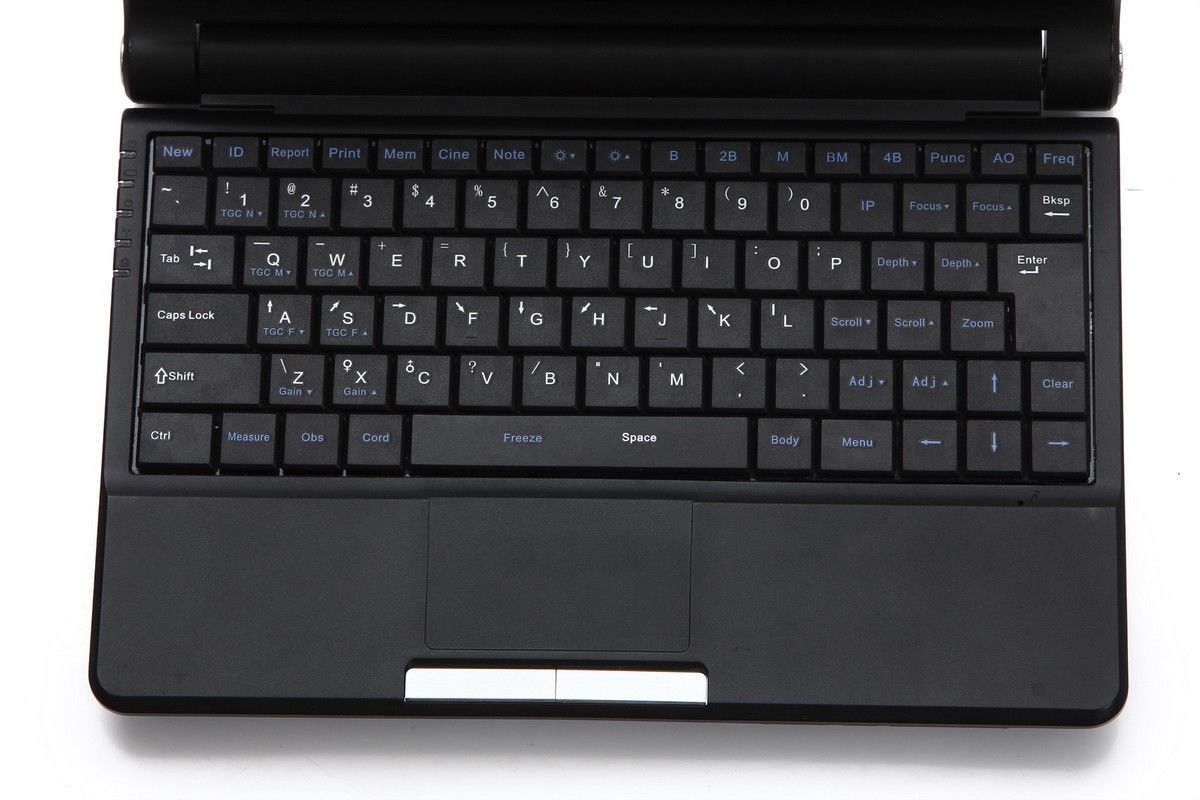

Model: RUS-9000F

Display /Monitor / Screen: 10.1-inch high-resolution TFT LCD

Probe frequency: Probe frequency